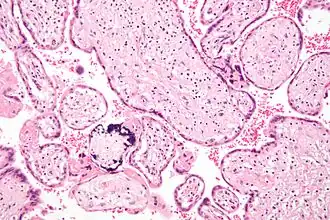

![]() Микрофотография плацентарной инфекции (плацентарный ЦМВ) | |

Инфекцию можно выявить микроскопически путём обнаружения внутриядерных включений. При окраске гематоксилин-эозином тельца включений становятся темно-розовыми, их называют «совиными глазами»[9].

Микрофотография цитомегаловирусного плацентита.